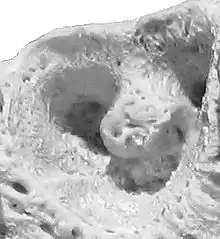

Alvéolo do segundo pré-molar de um bovino.